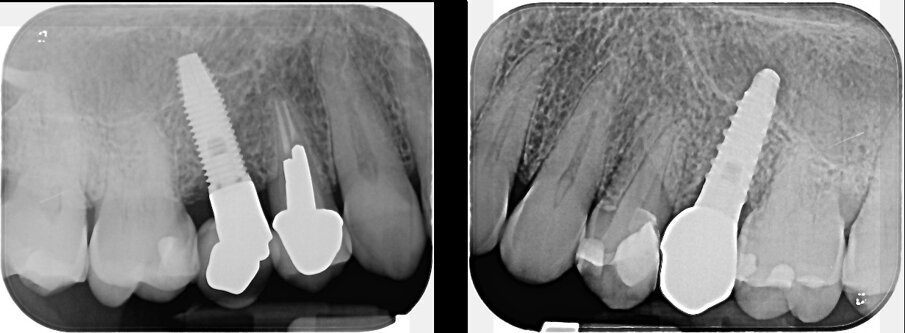

Non si evidenziava trauma occlusale o abitudini parafunzionali. La valutazione radiografica (Fig. 3) aveva rilevato una lieve perdita di osso marginale (MBL) distale dell’impianto 15. L’impianto 25 non era affetto da riassorbimento osseo. In accordo con il World Workshop of Peri-Implant Case Definitions12 del 2017, al paziente era stata fatta una diagnosi di mucosite peri-implantare per l’impianto 25 e di peri-implantite in fase precoce sull’impianto 15. Il difetto osseo a carico dell’impianto 15 può essere classificato come Classe Ia (difetto infraosseo - deiscenza buccale) Grado S (<25% della lunghezza dell’impianto)13. La paziente è stata trattata con una terapia parodontale e peri-implantare non chirurgica con applicazione topica di antimicrobici. Il full mouth debridement comprendeva ablazione del tartaro tramite strumenti a ultrasuoni e strumenti manuali. In particolare, sugli impianti, sono stati utilizzati delle curettes in titanio e un dispositivo air-polishing con polvere di eritritolo (Air-Flow Plus, EMS). Successivamente, è stata eseguita un’applicazione topica di XAN-CHX gel (Chlosite, Ghimas) all’interno dei solchi gengivali di entrambi gli impianti con un ago non traumatico dalla punta smussa (Fig. 4).

Fig. 3 - Condizione radiografica degli impianti 15 e 25 al baseline.